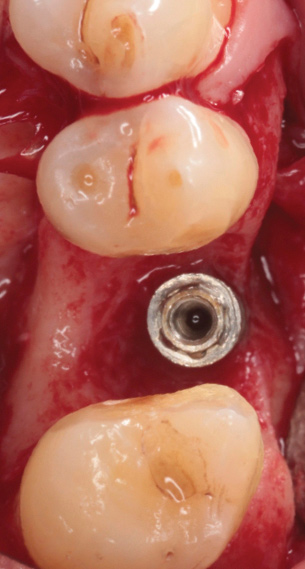

Peri-Implantitis Treatment

Following a similar paradigm of treating peri-implantitis the same way that periodontitis is regularly successfully treated, based on the mechanical removal of biofilms adhered to implant/abutment surfaces, different protocols of nonsurgical implant debridement using different mechanical, physical, and chemical mechanisms have been evaluated (Figure 12 through Figure 15). In general, the use of different protocols combining treatments aimed to decontaminate the implant surface (eg, mechanical, lasers) and control the infection process (eg, antiseptics, antibiotics) have shown clinical and significant improvements in the commonly used surrogate outcomes (mean reductions in PPD of around 1.2 mm and mean reductions in the scores of BOP of about 50%) but have not resulted in disease resolution18 or a high degree of predictablility.19 There is currently no specific nonsurgical therapy that has shown efficacy in the resolution of peri-implantitis, and the clinical improvements reported in the clinical studies were not sufficient for the arrest of the disease, leaving the standard of care in the treatment of peri-implantitis as surgical in most cases.20

Fig 14. After removing the prosthesis, presence of peri-implant plaque and calculus.

Figure 14

Fig 15. Access flaps to allow mechanical debridement of implant surfaces.

Figure 15